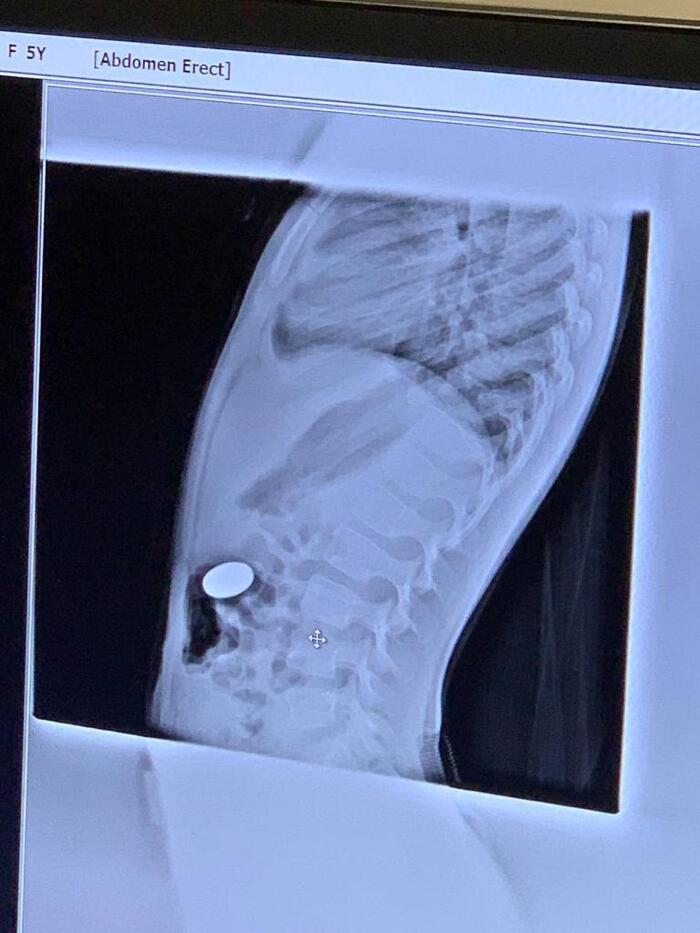

Через 20 минут после операции, в приемное отделение залетают ошарашеные родители с чадом около 4-5 лет. Монету проглотила.

Делаем Рентген

*скрепка не внутри, она для ориентации*

Я хмуро посмотрел на рентгенолога. Рентгенолог посмотрел на снимки, а потом на меня (искра, буря, безумие) - В поперечно-ободочной. Сама выйдет. - заключил он.

Посмотрели. 5ти Рублевая монета в желудке. Достали без происшествий. Отпустили с богом.